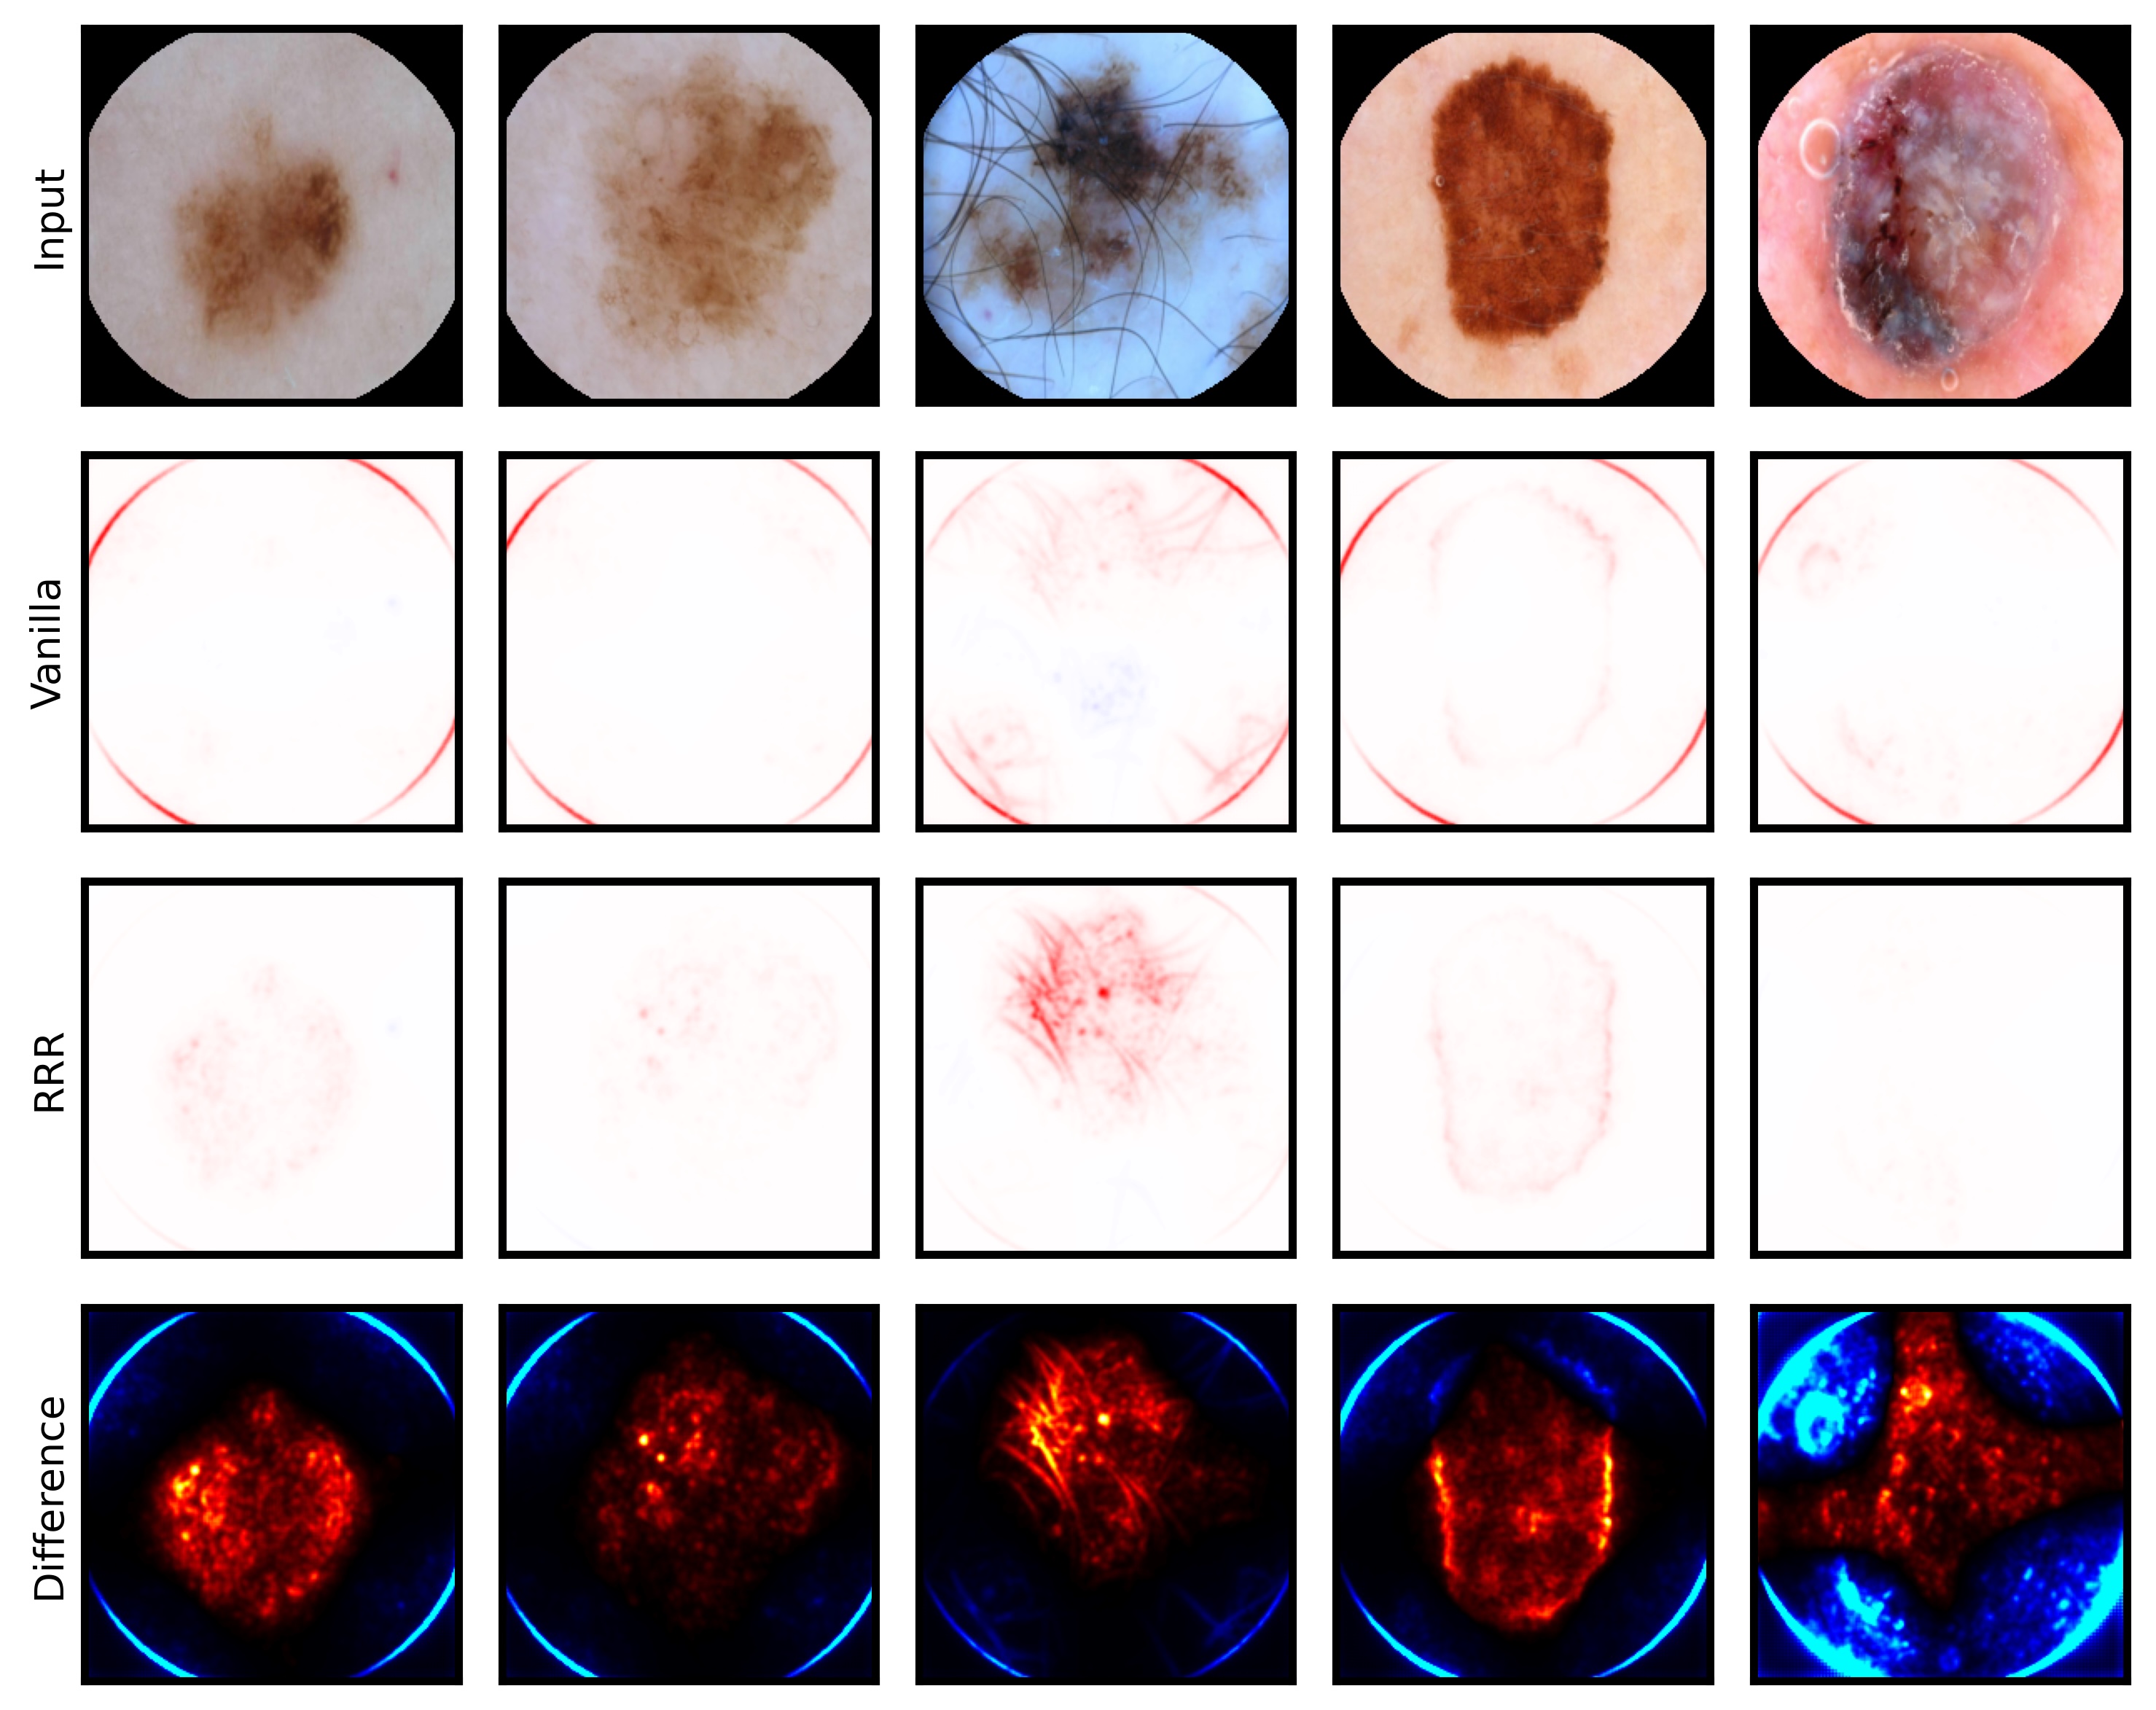

6.4 Spatial Bias Localization

To spatially localize biases in input space with CAVs, we compute local explanations for the element-wise product of latent activations and concept direction (see Eq. 2). We use the controlled artifacts, specifically timestamp (HyperKvasir) and micropscope (ISIC2019) with ground truth concept localization masks for evaluation. We compute (1) the percentage of relevance within the ground truth mask and (2) the Jaccard index, or Intersection over Union (IoU), of the binarized localization mask with the ground truth. In Fig. 9, we report both metrics using CAVs computed on different layers of VGG16 and ResNet50. The layer choice for concept representations is key, as for example middle layers perform better to localize timestamps and earlier layers are more effective to localize the microscope. In comparison with Fig.7, we find that the optimal layer for bias localization may differ from the one for sample retrieval. Interestingly, the IoU for the microscope artifact is consistently low, as models primarily focus on the border of the circle instead of the entire area, as indicated by qualitative results in Appendix A.6.3. Unlike artifact relevance, the IoU metric also measures how much of the expected areas the computed mask does not cover.

6.5 Bias Mitigation

We unlearn detected biases using the methods summarized in Sec. 5. We utilize RRR as input-gradient-based bias mitigation approach for localizable artifacts and the ClArC framework for all artifacts, representing biases in latent space with CAVs. Specifically, we consider the penalty-based approach RR-ClArC and the training-free model editing methods P-ClArC and rP-ClArC. To measure the bias mitigation effect, we compute several metrics inspired by prior work [59]. First, we compare the accuracy on a clean (bias-free) and a biased test set, where the bias is artificially inserted into samples from all classes. Models impacted by spurious correlations are expected to perform poorly on the biased test set. In addition, we measure the model’s sensitivity towards the bias concept by computing (1) the percentage of relevance, measured via LRP, on the artifact region using ground truth masks, and (2) the TCAV score [47]. The latter is reported as , where 0 indicates no sensitivity and higher values reliance on the artifact. Low scores are preferred after bias mitigation. The results are compared to a Vanilla model that is finetuned without a bias mitigation loss term. In Tab. 1, we report results for ResNet50 models in the controlled settings with ISIC2019, HyperKvasir, and CheXpert. For RRR, we use ground truth bias localization masks and refrain from reporting results for CheXpert, as we consider the brightness artifact unlocalizable in input space. The results confirm that all models initially rely on the spurious correlation, indicated by a large gap between clean and biased accuracies for Vanilla models. All bias mitigation approaches improve the accuracy on the biased test set while maintaining high accuracy on the clean test set, demonstrating reduced reliance on the targeted biases. This is supported by decreased artifact relevance and . Qualitative results visualizing the decrease in artifact reliance with input relevance heatmaps and additional quantitative results for other model architectures and ECG data are provided in Appendix A.6.4.